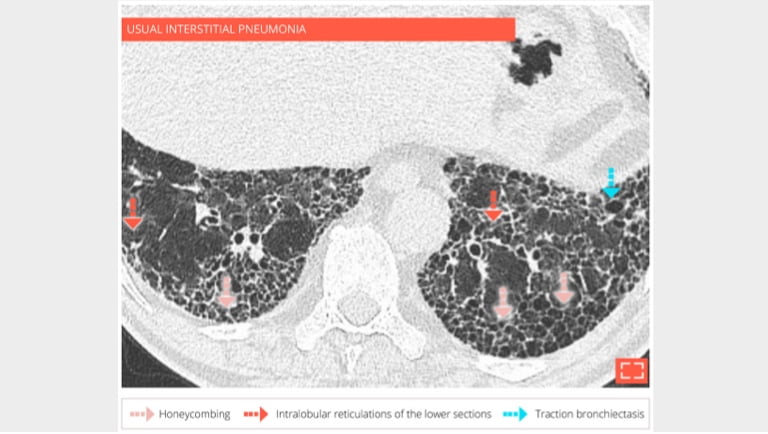

69-year-old man with usual interstitial pneumonia. Subpleural honey combing is associated with reticular pattern.

3. Honeycombing

Honeycombing

Sagittal reformation in the same patient showing the preferential subpleural and basal distribution.